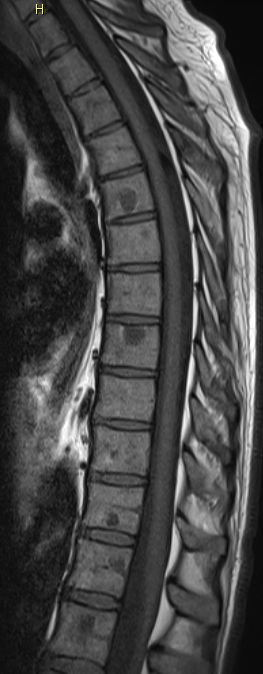

| Knochen - Metastasierung | ![]() |